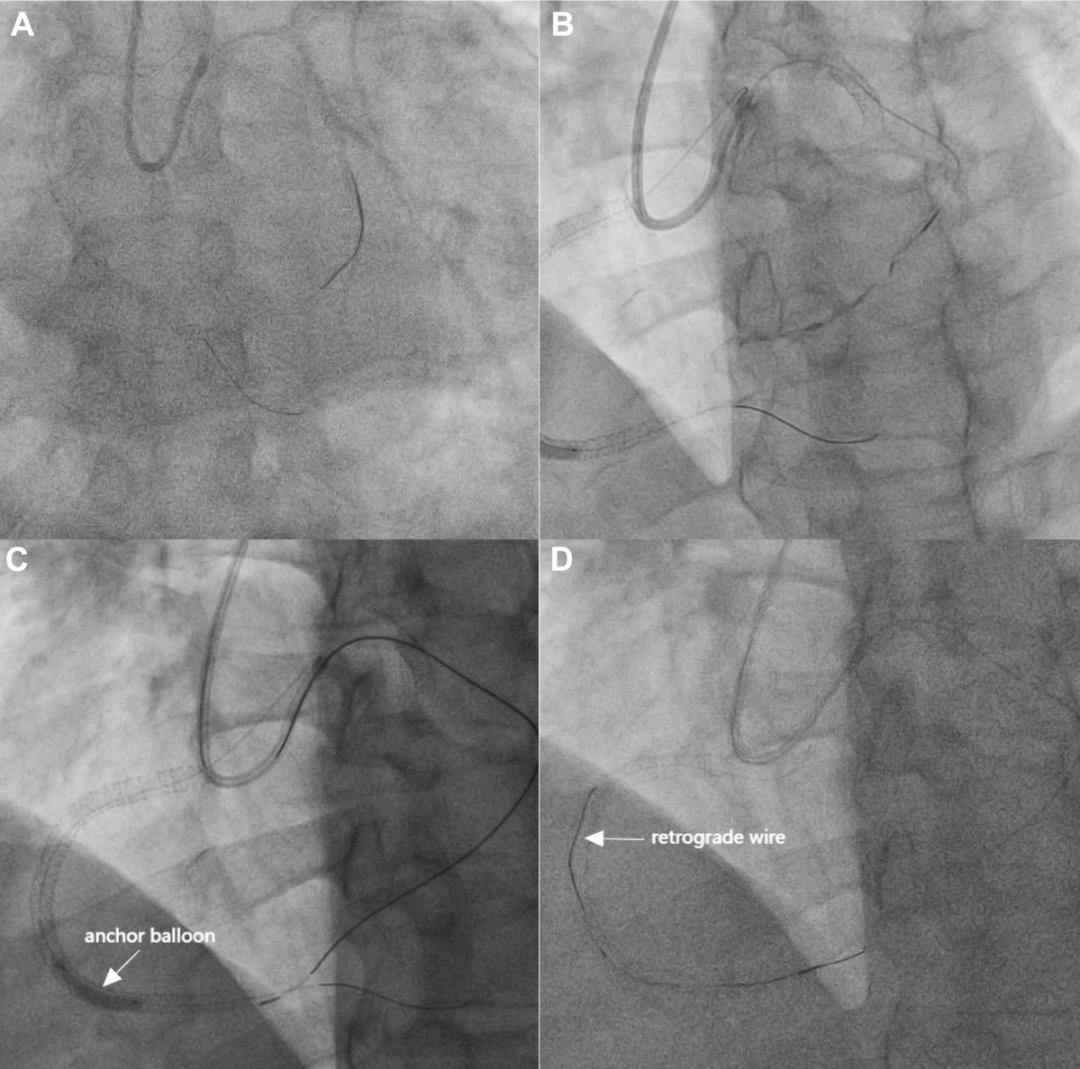

第二步:通过侧支循环,建立逆向通道

通过这根AL 0.75指引导管,在微导管冒烟引导下,将Suoh 03导丝成功通过心外膜侧支循环送至远端RCA,随后顺利完成逆向微导管跟进(图3A至3C,视频2)。

图3 通过心外膜侧支建立逆行通道并成功到达RCA近端

(A至C)Suoh 03导丝成功通过心外膜侧支到达RCA远端,随后逆行微导管成功跟进。(D)逆行导丝成功推进至RCA近端。

之后,将逆向导丝交换为Bingoreach 6导丝,并成功将其逆向通过闭塞段,推送至RCA近端。至此,逆向通道完全建立(图3D)。

第三步:逆向引导正向,完成病变开通

随后,AL 0.75指引导管被重新调整回RCA开口,撤回锚定球囊,将逆向微导管送入AL 0.75指引导管内。

采用反向rendezvous(会师)技术,正向微导管被引导至RCA远端(图4A、4B,视频3)。

图4 正向导丝成功送达RCA远端

(A)AL 0.75指引导管中的反向rendezvous技术。(B)正向微导管通过逆向导丝送达RCA远端。(C和D)正向工作导丝成功送达RCA远端。